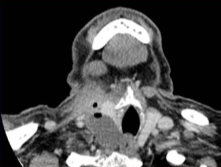

严重并发症【Baek JH 2013】声音改变 结节破裂 结节破裂脓肿形成 甲状腺功能减退 支气管神经丛损伤 ![]() 轻度并发症【Baek JH 2011】血肿 呕吐 皮肤灼伤 发热 典型反应疼痛:是最常见的副作用,2-60%【Nixon IJ 2018】,疼痛可导致2%的治疗停止【Tarantino L 2008】。 可以要求麻醉师在场,或不需要麻醉师,后者可以减少住院话费,也减少麻醉风险。也存在如何维持良好的忍耐性。 ![]() 良好的包膜下麻醉可以减少疼痛

迷走神经反射咳嗽《超声引导射频消融治疗良性甲状腺结节所的并发症:多中心研究》 ![]() 甲状腺消融并发症防治